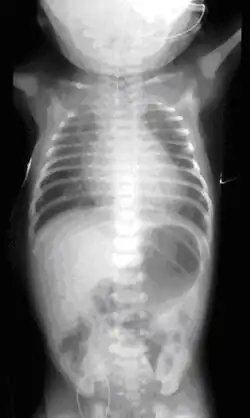

Plain X-ray of the chest and abdomen showing a feeding tube unable to move beyond an upper esophageal pouch.

On plain X-ray, a feeding tube will not be seen pass through the esophagus and remain coiled in the upper oesophageal pouch.[11]